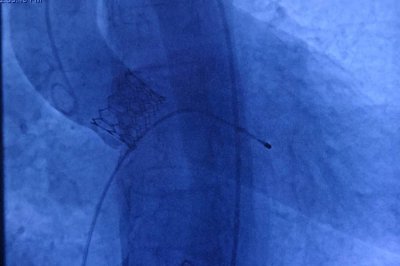

TAVI yöntemiyle kalp hastası yaşlılar sağlığına kavuşuyor

Aort kapak darlığının yaşla birlikte arttığını belirten Kardiyoloji Uzmanı Prof. Dr. Hasan Pekdemir, ameliyatsız gerçekleştirilen TAVI (Transkateter Aort Kapak İmplantasyonu) yöntemiyle hastalara büyük bir konfor sunduklarını ifade etti.